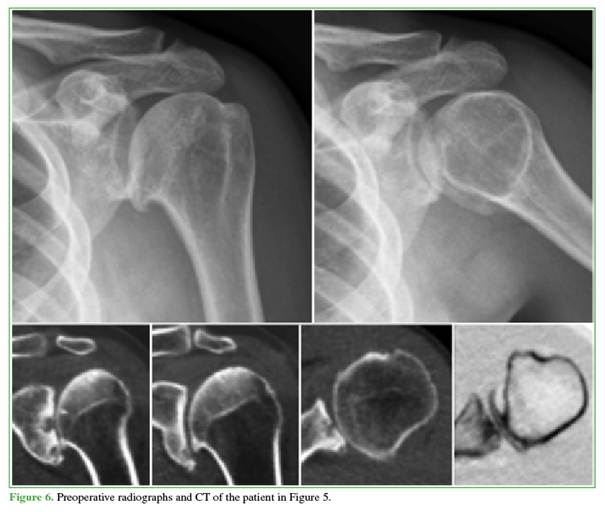

Active range of motion also improved. Forward elevation increased from 70.0° ± 25.0° preoperatively to 135.3° ± 24.8° at 12 months. Abduction rose from 57.2° ± 5.8° to 103.4° ± 9.0°. External rotation with the arm adducted improved from 25.1° ± 2.5° to 55.0° ± 4.6°. Internal rotation, graded on an ordinal scale, improved from 1.48 ± 0.50 to 4.04 ± 0.72 over the same period (Figures 6 and 7).

Radiographic findings: preoperatively, all 25 shoulders had Samilson–Prieto12 grade-3 osteoarthritis (loss of joint space, cysts, and osteophytes) (Figures 6 and 7).

Seven had asymmetric glenoid wear (Walch type B1 in 4 and B2 in 313). In addition, seven shoulders had moderate subluxation and one had severe subluxation. Postoperatively, subluxation resolved in 22 shoulders and persisted mildly in three. Mean glenohumeral joint space increased from 1.2 mm (range, 0–3) to 3.4 mm (range, 1–5) (Figure 8).